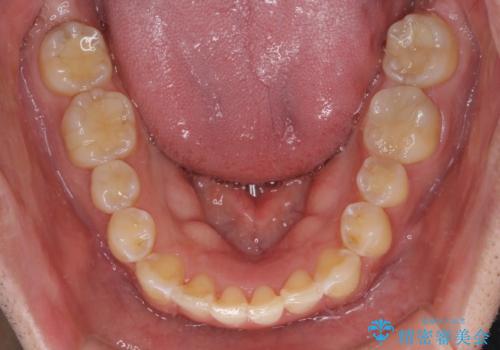

- 前歯のデコボコを強い咬みしめを気にして来院された患者様です。

インビザラインを用いて、前歯の叢生を解消するとともに、ディープバイトを改善していくこととしました。

ディープバイトが改善されたことで、顎への負担が軽減され、更には上顎前歯の突出感も改善することができました。

矯正治療後には欠けてしまった修復物をセラミックインレーにて修復治療しました。